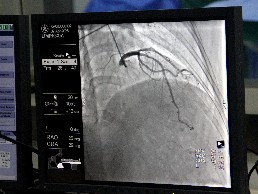

造影成像

冠状动脉造影是诊断冠心病的权威手段,可为不典型心绞痛、无创检查难以明确的冠脉病变等提供可靠诊断依据,具有创伤小、诊断精准、经济性佳等优势。